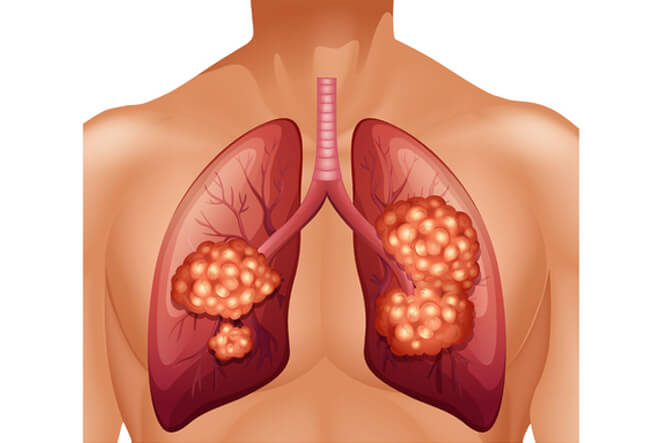

Respiratory diseases

Respiratory diseases are conditions that affect any of the processes involved with breathing. If you or someone you know are one of the 1 in 6 New Zealanders that lives with a respiratory condition, here you can find some useful information on how to manage the condition well.